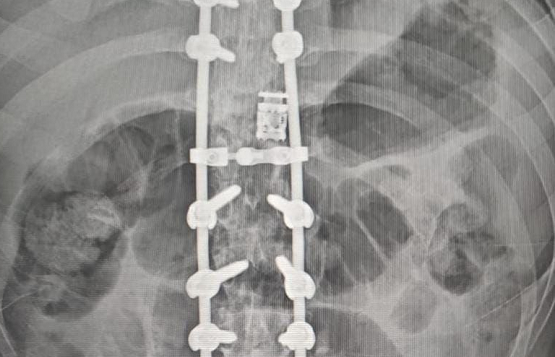

Dr. Somashekar D is an experienced spine surgeon in Bangalore. He is currently practising as a Consultant - Spine Surgery at Manipal Hospital Jayanagar, Bangalore. With nearly 10+ years of expertise in spine care, Dr. Somashekar has established himself as a highly skilled spine surgeon, contributing to over 1,500+ spine surgeries independently, ranging from simple decompressions to complex spinal reconstructions. His practice is deeply rooted in precision-based techniques and evidence-guided clinical protocols, ensuring both safety and long-term functional outcomes for his patients. He is a top spine surgeon in Jayanagar.

We offer comprehensive treatment for spine issues that is on par with any leading spine center worldwide. Our services encompass both non-surgical and surgical treatments tailored to address your specific condition. Our expertise covers a wide range of spine surgeries, including minimally invasive spine surgery, cervical spine surgery, scoliosis surgery, and complex spine surgeries.

• Spine trauma

Covers a wide range of spine surgeries, including complex spine surgeries.